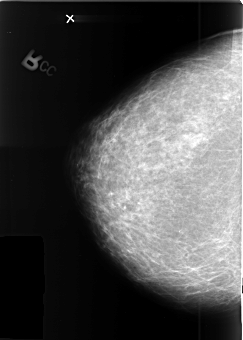

B_3410_1.RIGHT_CC

B_3410_1.LEFT_CC

LEFT_CC LINES 4176 PIXELS_PER_LINE 2776 BITS_PER_PIXEL 12 RESOLUTION 50 OVERLAY

FILE: B_3410_1.LEFT_CC.OVERLAY

TOTAL_ABNORMALITIES 1

ABNORMALITY 1

LESION_TYPE MASS SHAPE ROUND MARGINS OBSCURED

ASSESSMENT 3

SUBTLETY 5

PATHOLOGY MALIGNANT

TOTAL_OUTLINES 1

BOUNDARY